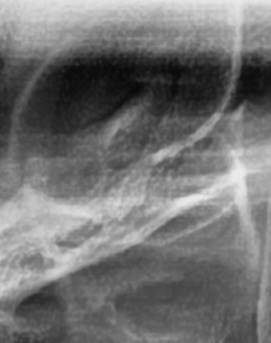

어금니 뒤 잇몸 부음의 문제는 사랑니가 원인이 되는 경우도 많은데 사랑니는 특히 현대인들의 경우 제대로 나오지 못하고 매복되는 경우가 많으며 완전히 나오지 않은 사랑니는 잇몸 속에서 자라면서 주변 잇몸을 자극할 수 있고, 일부만 노출되면 음식물이 끼면서 염증이 생기기도 하며 특히 어금니 뒤쪽 잇몸이 붓고 지속적으로 불편함을 느낀다면 사랑니로 인한 염증을 의심해 볼 수 있어요. 사랑니로 인한 문제의 경우 단순한 소염제나 구강 세정제로 해결되지 않고, 사랑니를 발치해야 잇몸 염증이 해결되는 경우가 많이 있어요

결론적으로는 통증이 심하거나 염증이 오래 지속되는 경우에는 치과를 방문해서 정확한 진단을 받는 것이 중요한데 단순한 잇몸 염증이라면 치석 제거와 항생제 치료로 호전될 수 있지만, 치주염이 진행된 경우라면 보다 적극적인 치료가 필요할 수 있어요. 만약 사랑니로 인해 잇몸이 자꾸 붓는다면 사랑니 발치를 고려해야 하겠고 사랑니가 완전히 매복되어 있다면 수술적인 방법으로 제거해야 할 수도 있어요. 특히 반복적으로 붓는다면 사랑니 검사를 받아보거나, 치과에서 정밀 검진을 통해 치주 상태를 확인하는 것이 필요하다는 점에서 어금니 근처의 잇몸이 반복적으로 불편하다면 꼭 치과를 찾아보시길 바라고 있어요